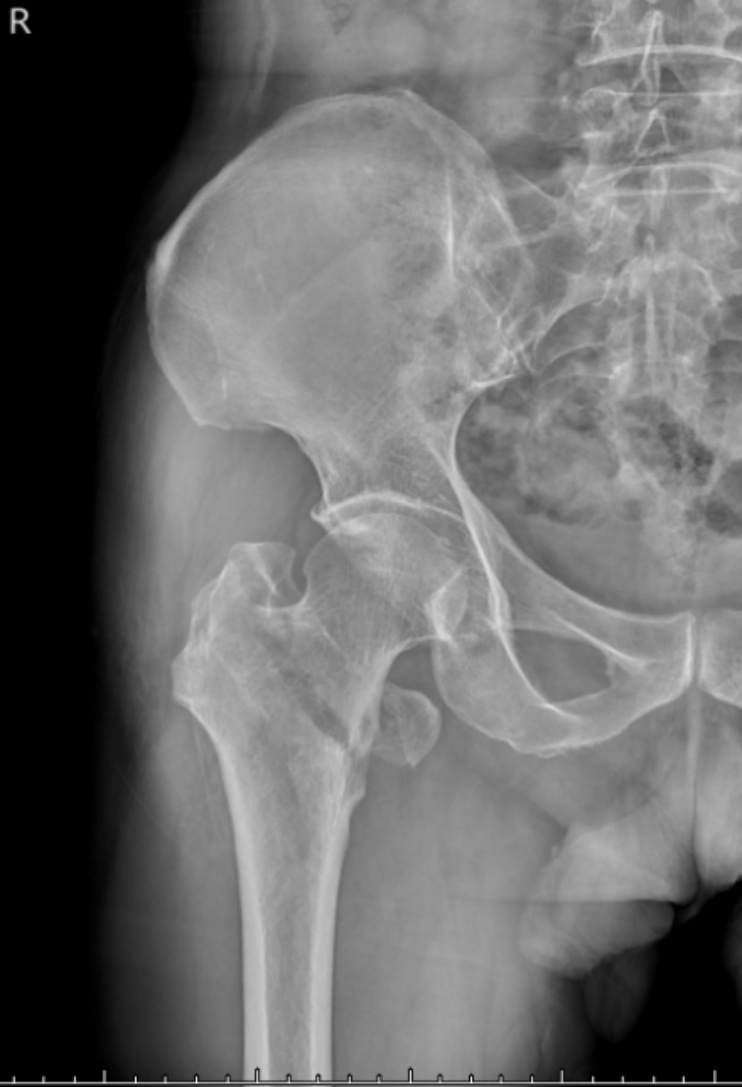

典型病例影像学表现见图1~10。图1为86岁女性右侧股骨转子间骨折(Evans Ⅲ型)患者,术前X线示骨折断端部分错位,术后X线示骨折位置可以及假体位置良好;图2显示了一名81岁男性患者,诊断为左侧股骨转子间骨折,类型为Evans V型,合并股骨干陈旧性骨折。患者接受了生物型加长柄半髋关节置换手术,并进行了股骨近端的钢丝捆扎内固定。术后X线示假体位置良好,股骨近端予钢丝捆扎固定;图3为87岁女性左侧股骨转子间骨折(Evans V型)患者,术后X线示假体位置良好,股骨大小转子骨折位置可,钢丝捆扎固定在位有效;图4为75岁女性左侧股骨转子间骨折(Evans V型)患者,术前X线示左侧股骨转子间骨折PFNA术后、骨折未愈合、内固定断裂。术后假体匹配良好,股骨近端钢丝内固定稳定可靠;图5为75岁男性左侧股骨转子间骨折(Evans IV型)患者,术后股骨大转子出现轻度位移,假体位置正常。图6为87岁男性左侧股骨转子间骨折(Evans V型)患者,给予DAA入路加长柄半髋关节置换,术前X线片,清晰地显示出左侧股骨转子间的骨折情况,术后X线影像,显示股骨的大小转子骨折位置良好,钢丝内固定装置在位稳定,假体位置良好;图7为77岁女性右侧股骨转子间骨折(Evans V型)患者,术前X线片显示右侧股骨转子间存在骨折且股骨大小转子均有累及和移位,术后X线片显示股骨小转子轻度移位,内固定装置位置稳定,假体位置良好;图8为70岁男性左侧股骨转子间骨折(Evans III型)患者,术前的X线片,清晰地显示了左侧股骨转子间的骨折情况,股骨近端髓腔钙化灶,术后假体位置满意;图9为77岁女性右侧股骨转子间骨折(Evans V型)患者,术前X线片,显示右侧股骨转子间及转子下部位骨折情况。术后假体匹配良好;图10为71岁男性右侧股骨颈骨折(Evans IV型)患者,术前X线片,显示右股骨转子间骨折的情况;术后X线表明股骨的大转子和小转子骨折位置保持良好,内固定装置稳固,术后假体位置正常。

(a) (b)

Figure 10. A 71-year-old male patient with right femoral neck fracture (Evans type IV). (a) Before surgery; (b) After surgery

10. 71岁男性右侧股骨颈骨折(Evans IV型)患者。(a) 术前;(b) 术后